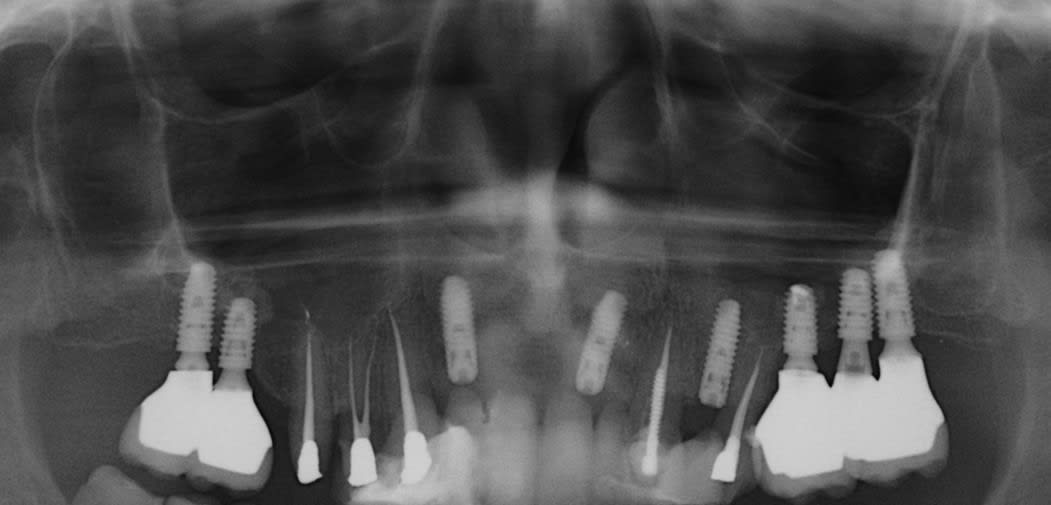

J'ai posé un implant via un summers ( 2-3mm d'os de base et implant 5x8 ) sur 26 et lors du controle post 3 mois je vois que la majorité du bio oss à disparu ( il reste quelques zones par ci par là)

et voila la radio

Honnêtement Je le sens pas ton truc :) je pensais que l’implant reposait complètement dans le vide sans rien autour. Là tu n’as pas que du bio oss autour. C’est de la fibro intégration sur les 2/3.

je peux me tromper, mais je ne pense pas voir un granulome à l'apex de l'implant mais une muqueuse hyperhémiée ou congestionnée, au dessus d'une zone osseuse qui me parait saine et semble faire plus de 2/3 mm..

après avoir longtemps (depuis 1989) pratiqué des fenêtres latérales, je ne fais pratiquement que des summers (exemple ci dessous) en laissant du temps à la cicatrisation et jusqu'à présent pas de soucis particulier, et avant d'aller "bricoler" dans un sinus pour retirer du biooss (que je n'aime pas du tout) et/ou du tissus de "granulation", je prends le temps, et si l'implant est stable je ne me pose pas de question.